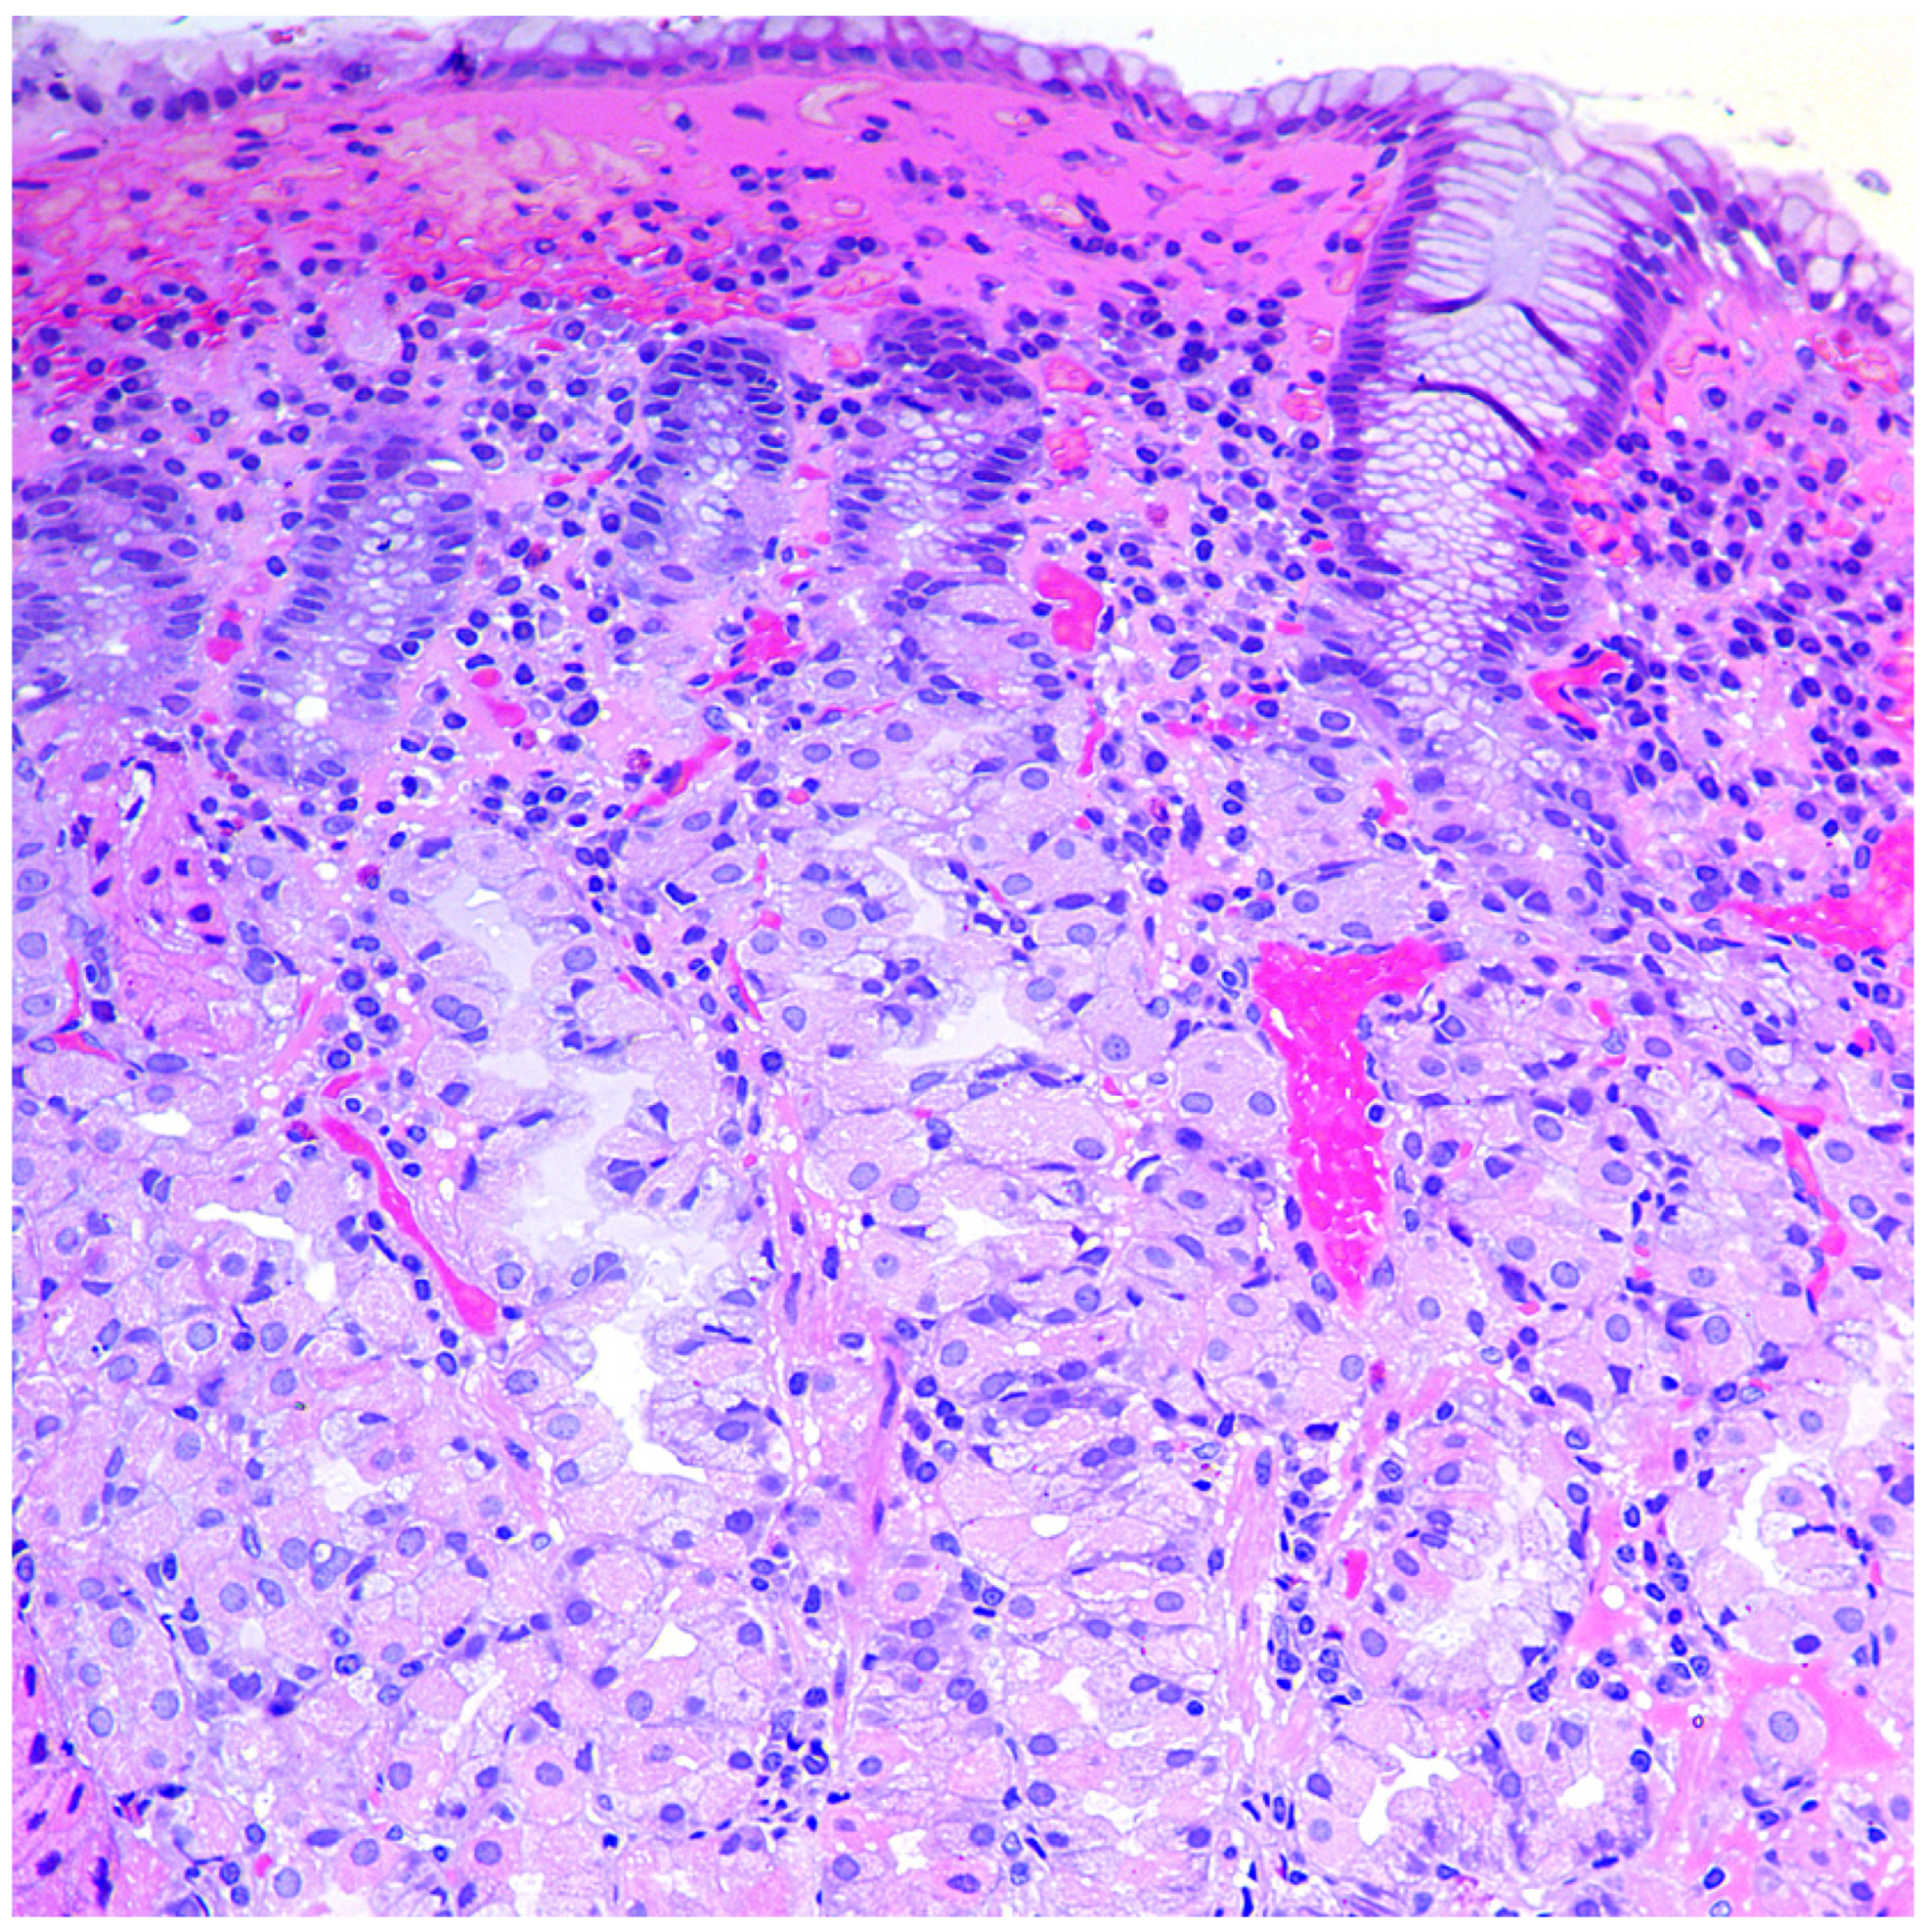

2.3. Morphological Examination

- Torbenson, M.; Abraham, S.C.; Boitnott, J.; Yardley, J.H.; Wu, T.T. Autoimmune gastritis: Distinct histological and immunohistochemical findings before complete loss of oxyntic glands. Mod. Pathol. 2002, 15, 102–109. [Google Scholar] [CrossRef]

- Stolte, M.; Baumann, K.; Bethke, B.; Ritter, M.; Lauer, E.; Eidt, H. Active autoimmune gastritis without total atrophy of the glands. Z. Gastroenterol. 1992, 30, 729–735. [Google Scholar] [PubMed]